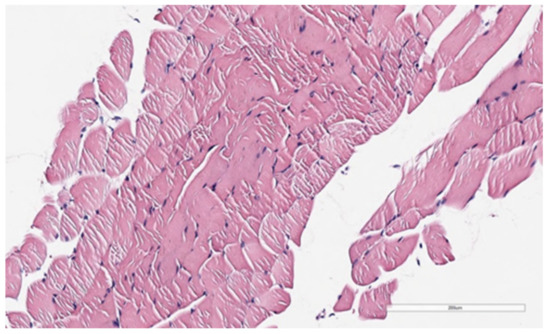

3.2. Observational Findings